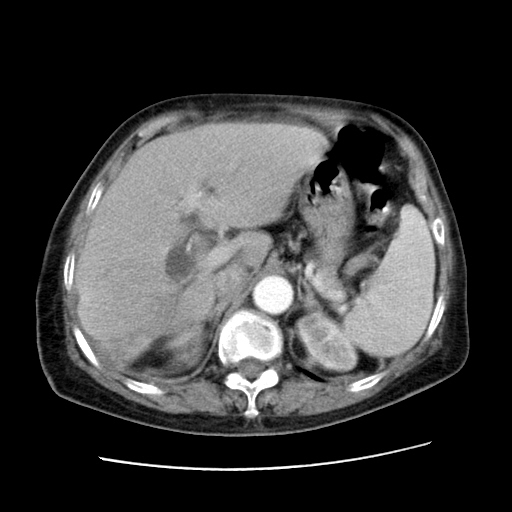

女,77.无不适

肝脏变异、异位胆囊,肝右叶肝内胆管结石并肝内胆管扩张。

肝右叶肝内胆管结石并肝内胆管扩张。

肝右叶肝内胆管结石并肝内胆管扩张

胆总管扩张

肝右叶肝内胆管结石并肝内胆管扩张。胆总管下段梗阻,考虑壶腹部占位。

右侧肝内胆管局限性扩张,其内密度不均匀,扩张的胆管壁增厚,考虑肝内胆管炎合并结石可能性大

肝右叶肝内胆管结石并肝内胆管扩张。胆总管下段梗阻,考虑壶腹部占位。支持